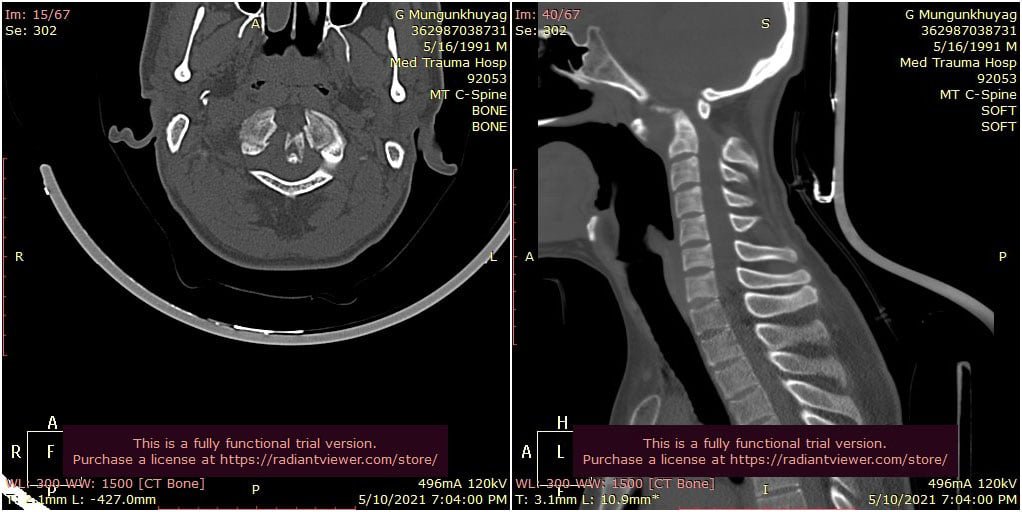

Гэмтэл Согог Судлалын Үндэсний төвийн зөвлөх эмч Ж.Оюунтөгс, Л.Бат-Эрдэнэ тасгийн эрхлэгчтэй, Б.Баттөгс ахлагчтай Хүзүү нурууны гэмтэл согогийн тасгийн хамт олон Монголд анх удаа хүзүүний нугалмын хугарал мултралыг арын хүрцээр дагз ястай хамт бэхлэх мэс заслыг амжилттай хийлээ.